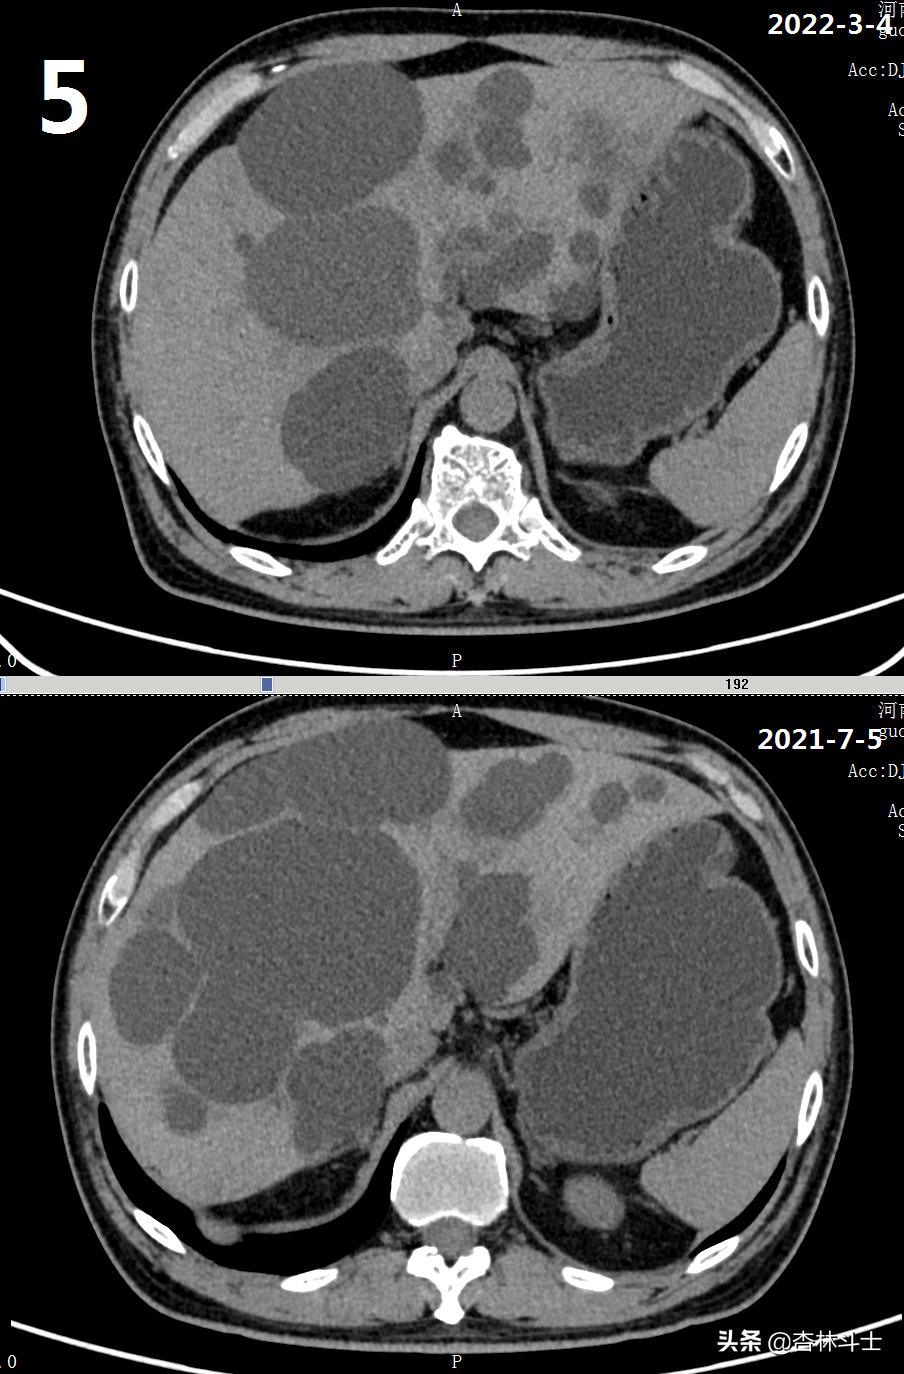

64岁退休银行职员,腹胀5年,加重2月,第二次入住我院消化内科。下图1-6为本次复查上腹部CT与2021-7-5肝囊肿经皮肝穿刺抽吸无水酒精硬化术前的对比图。

可明显看出,肝内囊肿较前减少,肝实质所占体积明显增加。